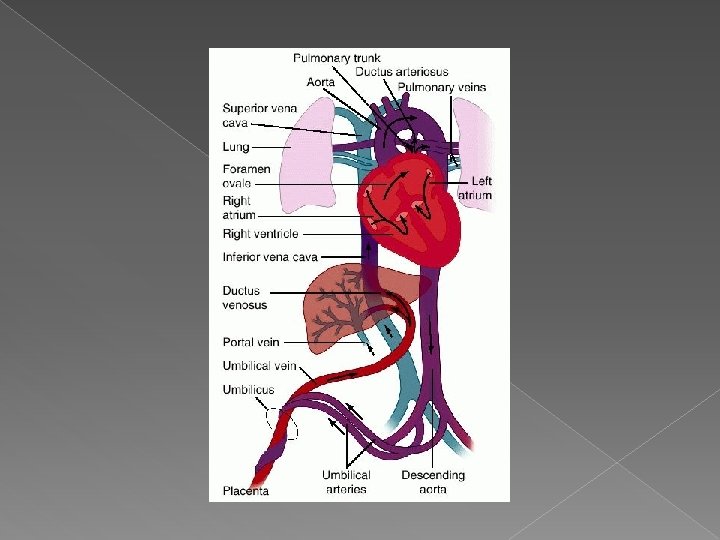

Fetal circulation Oxygenated blood enters the fetus through the umbilical vein � The ductus venosus partially bypasses the lever to send oxygen – rich blood to the right ventricle � The foramen ovale shunts some of the right atrial blood directly into the left atrium � The ductus arteriosus allows oxygen-rich blood from the pulmonary artery into the aortic arch to circulate throughout the fetus �

� Ductus Venosus: In the fetus, the ductus venosus shunts approximately half of the blood flow of the umbilical vein directly to the inferior vena cava. Thus, it allows oxygenated blood from the placenta to bypass the liver. In conjunction with the other fetal shunts, the foramen ovale and ductus arteriosus, it plays a critical role in shunting oxygenated blood to the fetal brain

� Foramen Ovale: a shunt from the right atrium into the left atrium � Ductus Arteriosus: a shunt connecting the pulmonary artery to the aortic arch. It allows most of the blood from the right ventricle to bypass the fetus's fluid-filled lungs

The fetal circulation, labeling the Foramen ovale, ductus arteriosus, and ductus venosus.

� Blood flow through the heart is proportioned as follows: › 60% of right atrial blood passes through the foramen ovale, into the left atrium, and into the systemic circulation. › 40% of right atrial blood enters the right ventricle: � 92% of main pulmonary artery volume bypasses the lungs via the ductus arteriosus and into the system circulation � 8% of the ventricular blood reaches the lungs